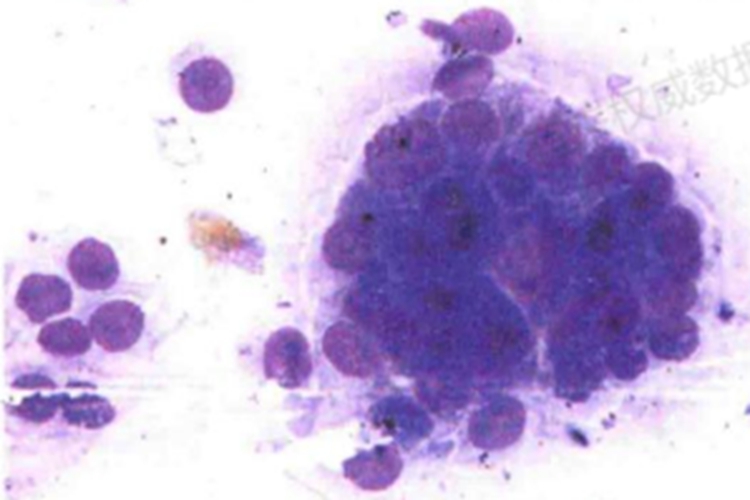

来源于腺体、导管或分泌上皮细胞的恶变。腺癌细胞常成堆分布,呈桑葚状、花瓣状;胞质内常含有多少不等的黏液空泡,常将核挤于一侧,呈戒指状。与鳞癌细胞相比,核增大、核畸形、核深染、核质比增大不明显。一般根据细胞的分化程度将腺癌分为高分化腺癌和低分化腺癌。